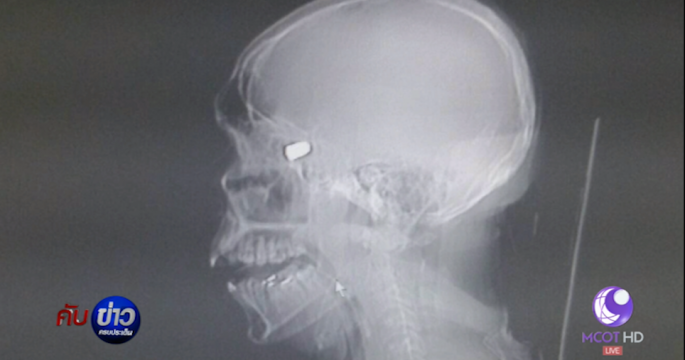

คู่รักหนุ่มสาวอยุธยาหยอกล้อกันก่อนนอน นำปืนลูกโม่ออกมาเล่น กระสุนลั่นเจาะหน้าผากแฟนสาวเสียชีวิตคาห้องนอน